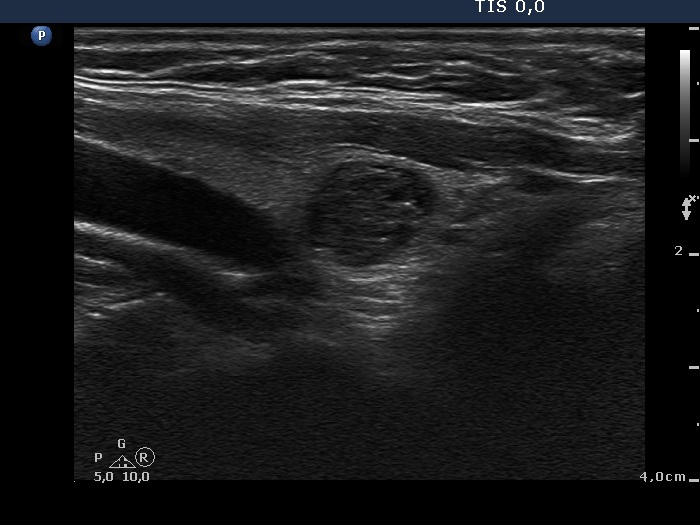

Benign cystic-colloid goiter (cytological diagnosis) - case 123 |

Intrathyroidal parathyroid adenoma (histological diagnosis) - case 1399 |

The synchronous presence of hyperechogenic lines and granules proves that these figures represent connective tissue while one in the ventral part does represent a colloid crystal.

There are a few hyperechogenic granules within the small lesion and we can see two much thinner lines, as well. These figures might be either punctate echogenic foci or non-specific granules of a normal connective tissue.